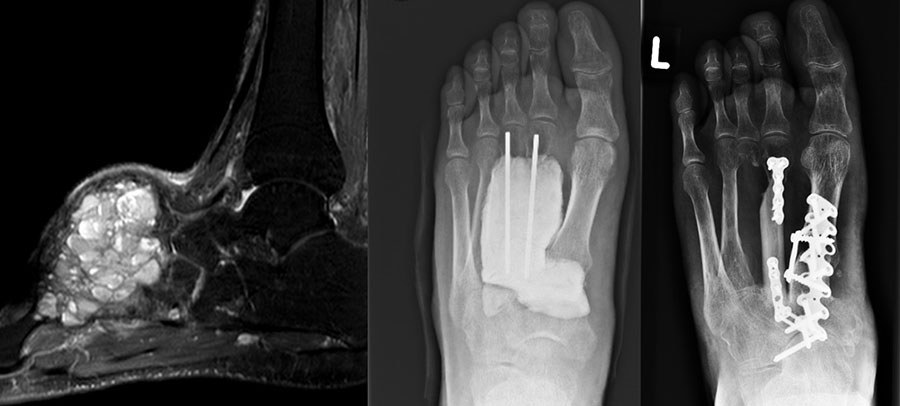

Weite Resektion

Bei der operativen Therapie maligner Neoplasien ist im Rahmen eines kurativen Therapie­ansatzes die weite Resektion zwingend erforderlich. Dabei richtet sich das jeweilige operative Vorgehen mit der nachfolgenden Rekonstruktion nach der Lokalisation des Tumors. Bei Läsionen im Bereich der distalen Tibia ist eine Segmentresektion des Knochens mit möglicher Überbrückung des Defekts durch Verwendung eines Tibia-Verschiebespans oder Fibula-Autografts und gleichzeitige Arthrodese im Bereich des oberen Sprunggelenks möglich. Aufgrund der hohen Belastung in diesem Extremitätenabschnitt ist eine Doppelung der Fibula und Anlagerung zusätzlicher Beckenkammspongiosa zu diskutieren (Burgkart, 2003). Bei Neoplasien im Bereich der distalen Fibula kann mit segmentaler Resektion des betroffenen Knochenabschnitts inklusive lateralem Malleolus und Durchführung einer tibio-talaren Arthrodese mit geringgradiger Extremitätenverkürzung meist ein funktionell gutes Ergebnis erzielt werden. Ist der Knochentumor im Bereich der posterioren Talusanteile lokalisiert so kann nach Osteotomie im Bereich des Talushalses unter Verkürzung der Extremität eine tibiocalcaneare Arthrodese mit Einbeziehung des restlichen Talus im Sinne einer Blair-Arthrodese durchgeführt werden 28. Bei Tumoren im Bereich des Calcaneus, die eine weitere Resektion notwendig machen, ist entweder eine Syme-Amputation oder die isolierte Resektion des Calcaneus mit Versorgung des entstandenen Defekts durch einen myo-cutanen Lappen und Verwendung spezieller Schuhe möglich (Burgkart, 2003). Ausgeprägte Befunden, die über die Höhe des oberen Sprunggelenks hinausreichen, erfordern selten eine distale Unterschenkelamputation (Abb. 10a-e). Die früheren Amputationsschemata, die von Amputationen in der distalen Hälfte des Unterschenkels abgeraten haben, besitzen heute keine Gültigkeit mehr 29. Dem Erhalt der Länge ist nach Beachtung einer entsprechenden Radikalität der Tumorresektion höchste Priorität zu bemessen. Bei Tumorlokalisation im Bereich des Mittelfußes können nach vollständiger Entfernung des jeweiligen Knochens Rekonstruktionen unter Verwendung autologer oder allogener struktureller Transplantate ("strut grafts") zu funktionell guten Mittelfußarthro­desen führen (Abb. 11) (Burgkart, 2003). Mit Ausnahme der großen Zehe können Amputationen der Zehen meist gut kompensiert werden. Amputationen in Höhe der Grund- und Mittelglieder der Kleinzehen sind wegen der Imbalance der Muskulatur mit sekundären Fehlstellungen zu vermeiden 29.